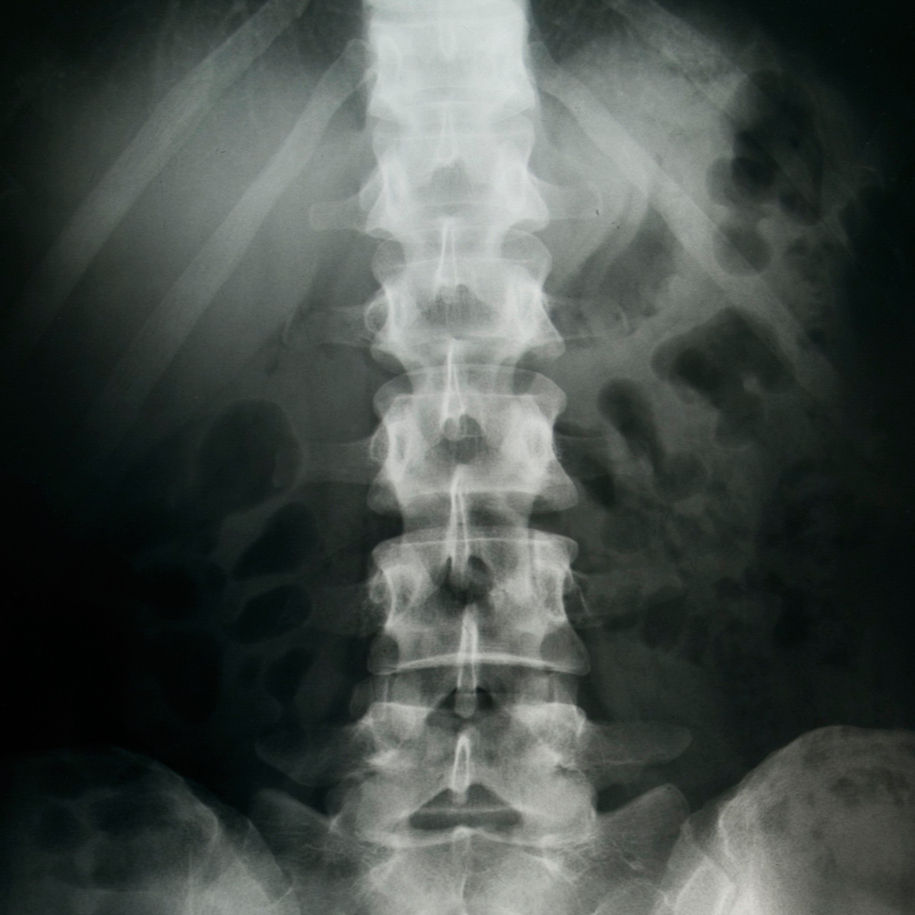

🧠 O Que é Exatamente o Trauma Raquimedular (TRM)?

Imagine a medula espinhal como a principal via de comunicação entre seu cérebro e o resto do corpo.

O TRM ocorre quando essa "estrada" é danificada, interrompendo o fluxo de informações.O resultado pode ser a perda de movimentos, de sensibilidade e do controle de funções vitais.

Exames de imagem (radiografia, tomografia e ressonância) para diagnóstico preciso.